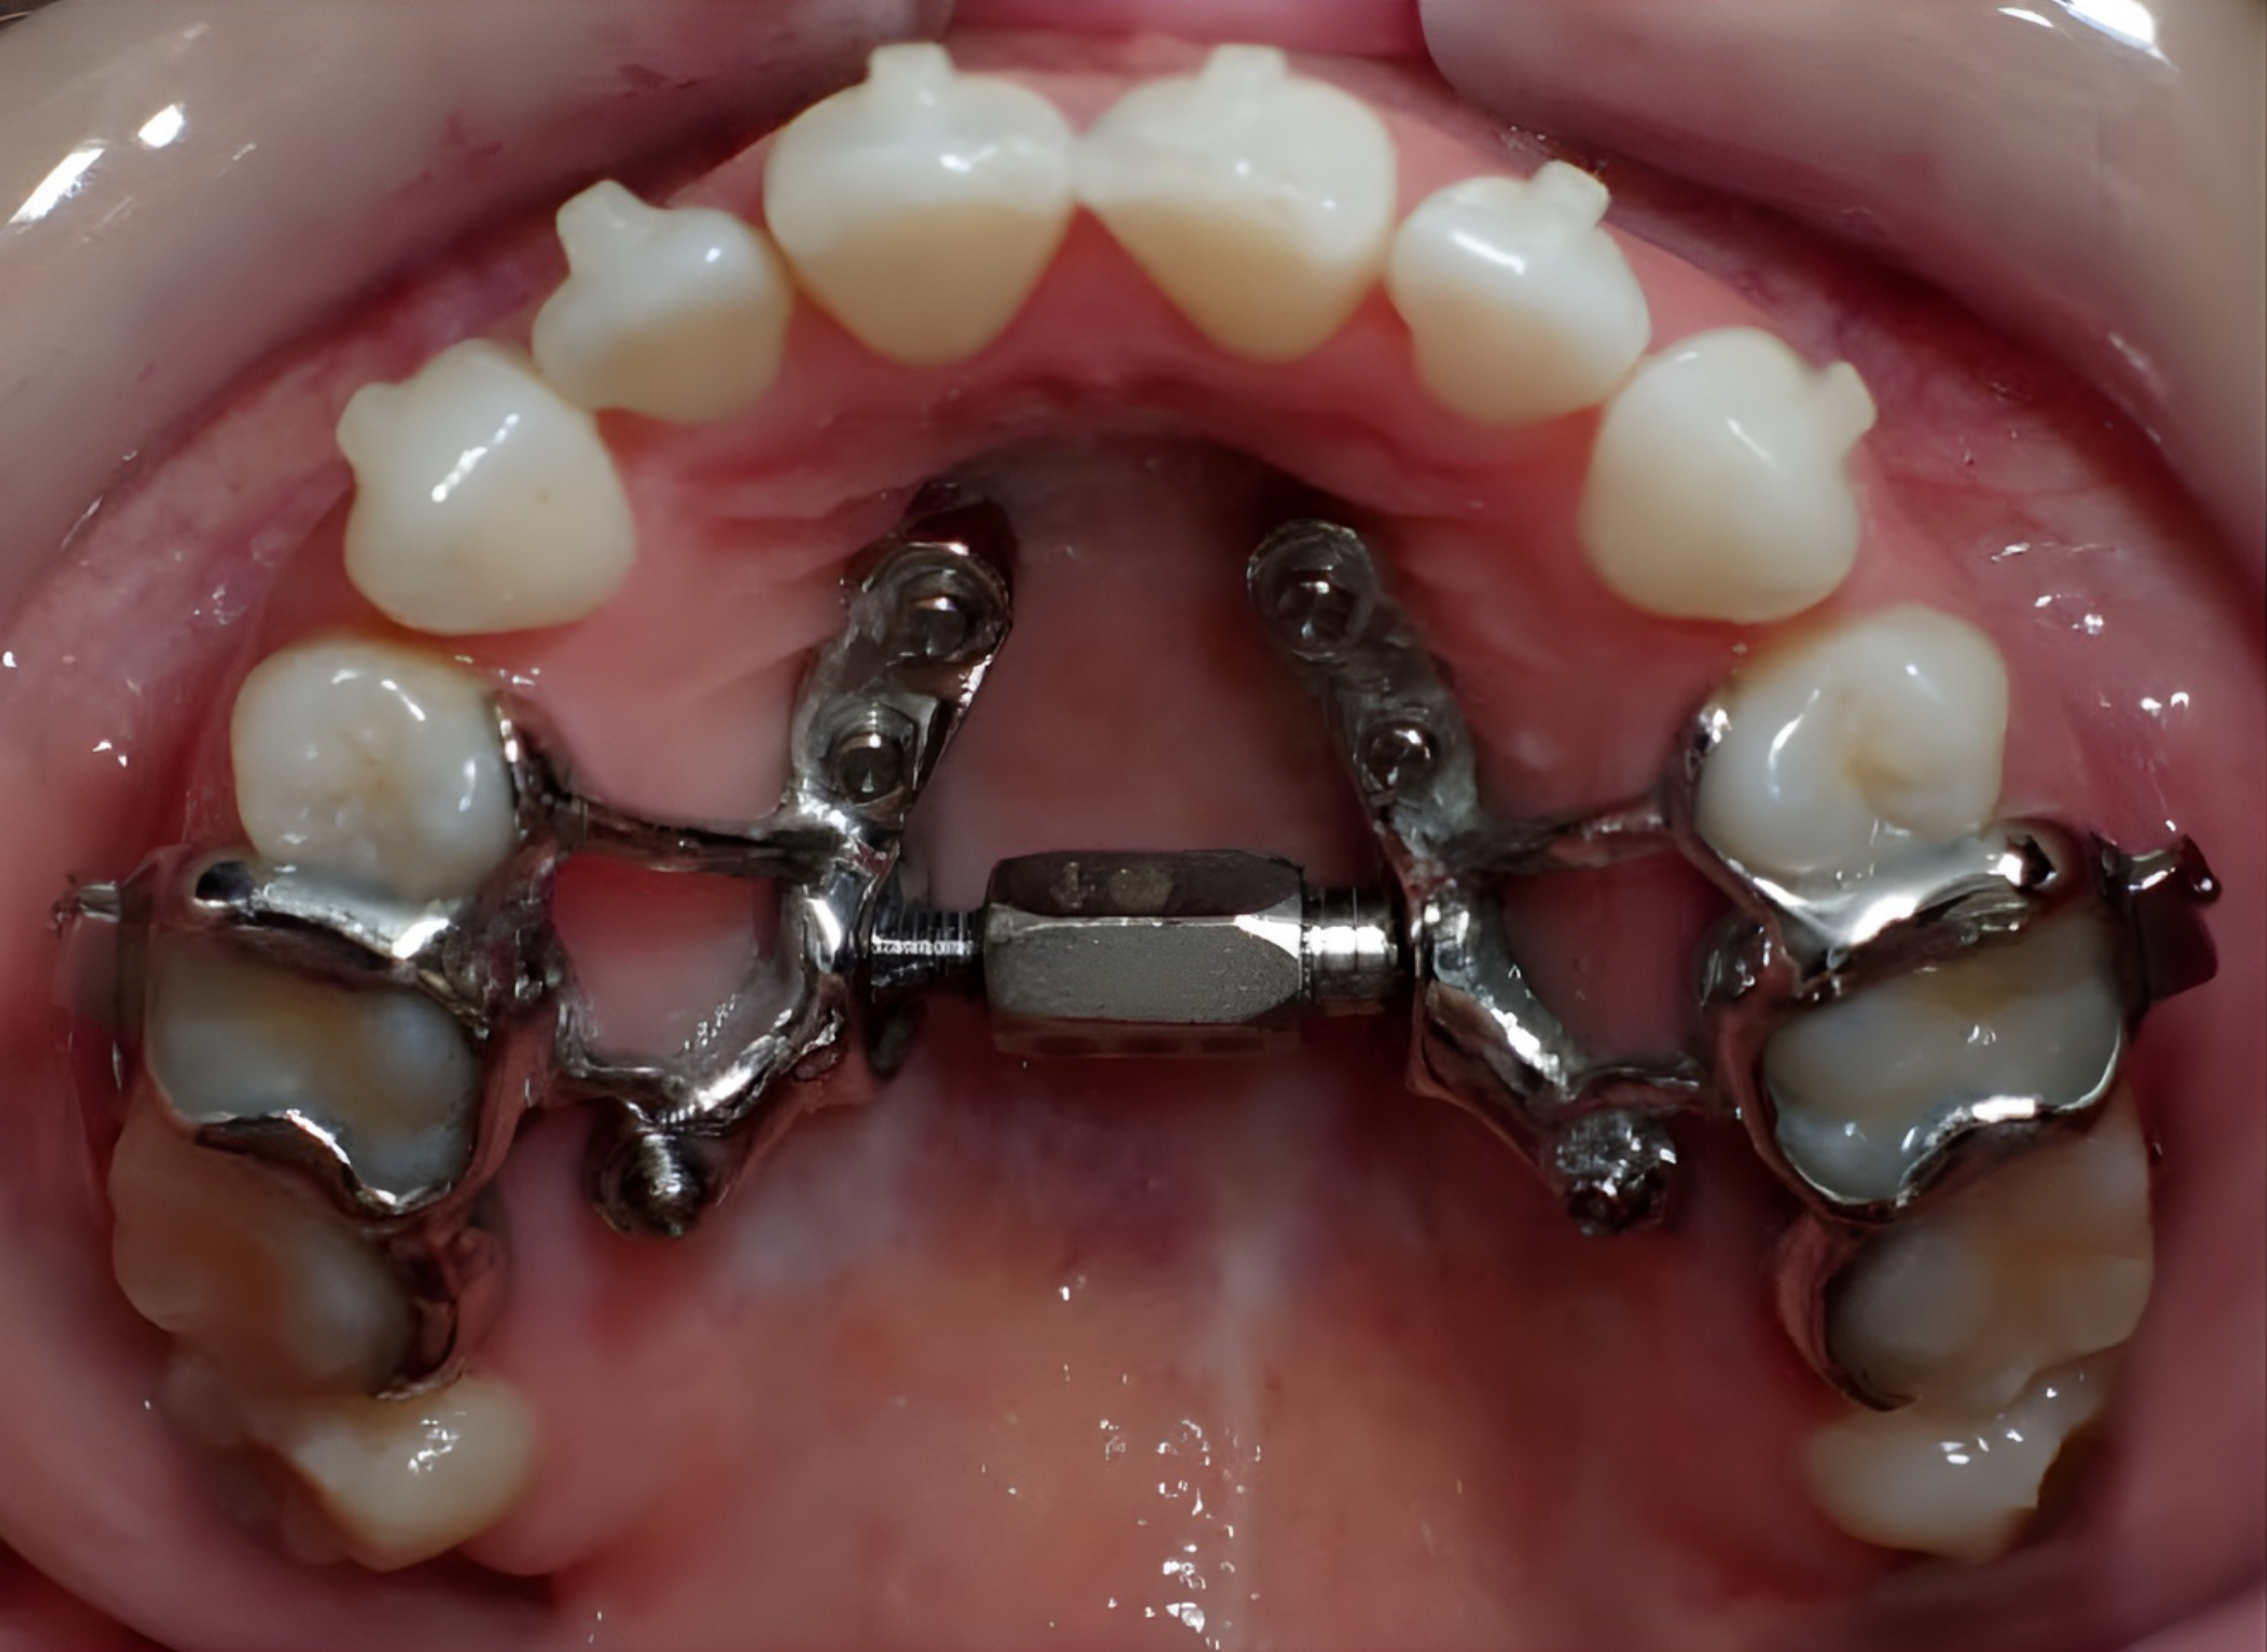

Custom 3D-Printed MARPE: How Is It Different and Why Consider It?

Custom 3D-printed MARPE represents a significant advancement over conventional expansion techniques. Because the appliance is individually designed rather than adapted from a standard template, treatment becomes more precise, efficient, and biologically guided. Customization allows clinicians to optimize implant placement in areas of strongest bone support, improving stability and reducing unnecessary pressure on teeth and soft tissues. Patients may benefit from increased comfort, fewer adjustments, improved hygiene access, and more predictable skeletal expansion. For many adolescents and adults seeking non-surgical jaw expansion, custom 3D-printed MARPE offers a modern, minimally invasive solution that combines digital planning with orthopedic precision.